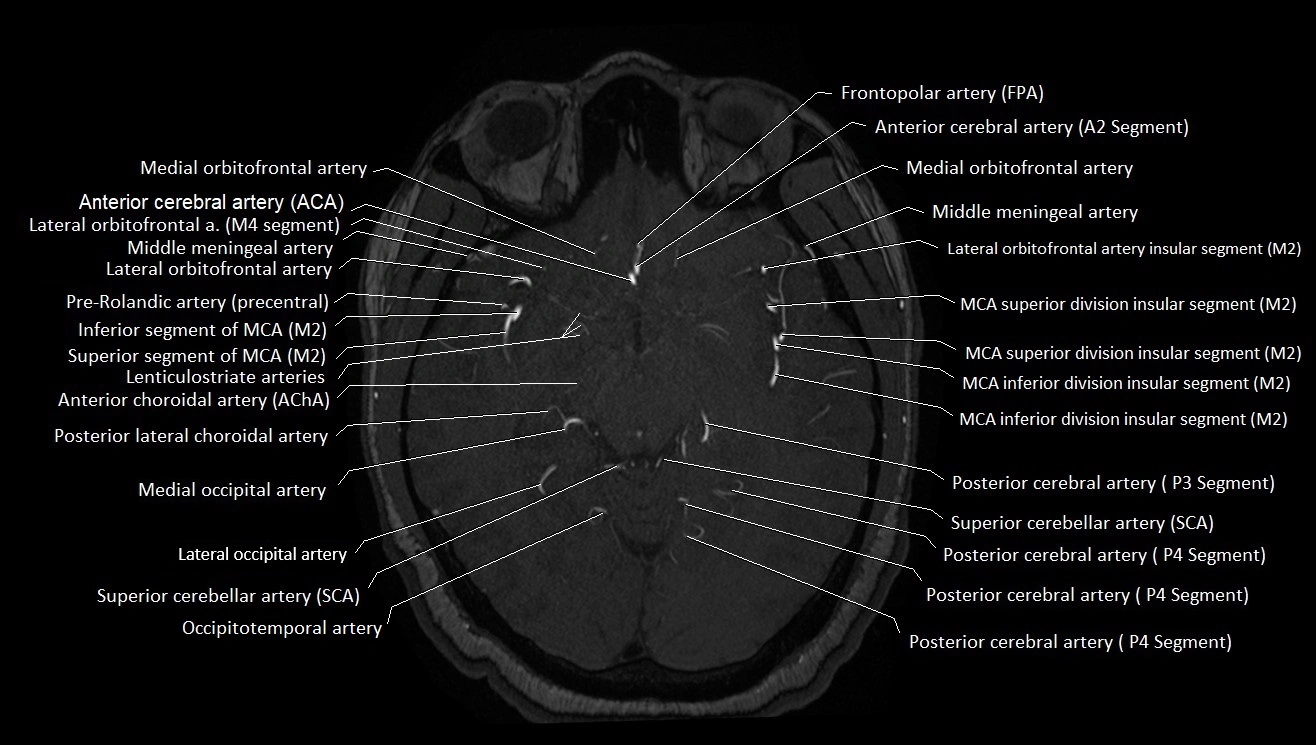

MRI Appearance

T1-weighted images:

• Vessel appears as a flow void (dark lumen) near the optic tract and temporal horn

• Surrounding parenchyma intermediate signal

T2-weighted images:

• Vessel lumen shows dark flow void

• Ischemic infarcts in its territory (internal capsule, thalamus) appear hyperintense

MRA (Magnetic Resonance Angiography):

• Flow-related enhancement makes the AChA appear as a bright, linear vascular signal against suppressed background

• High sensitivity for origin and proximal course; distal branches may be too small to resolve

• Detects stenosis, occlusion, aneurysm, AVM feeders